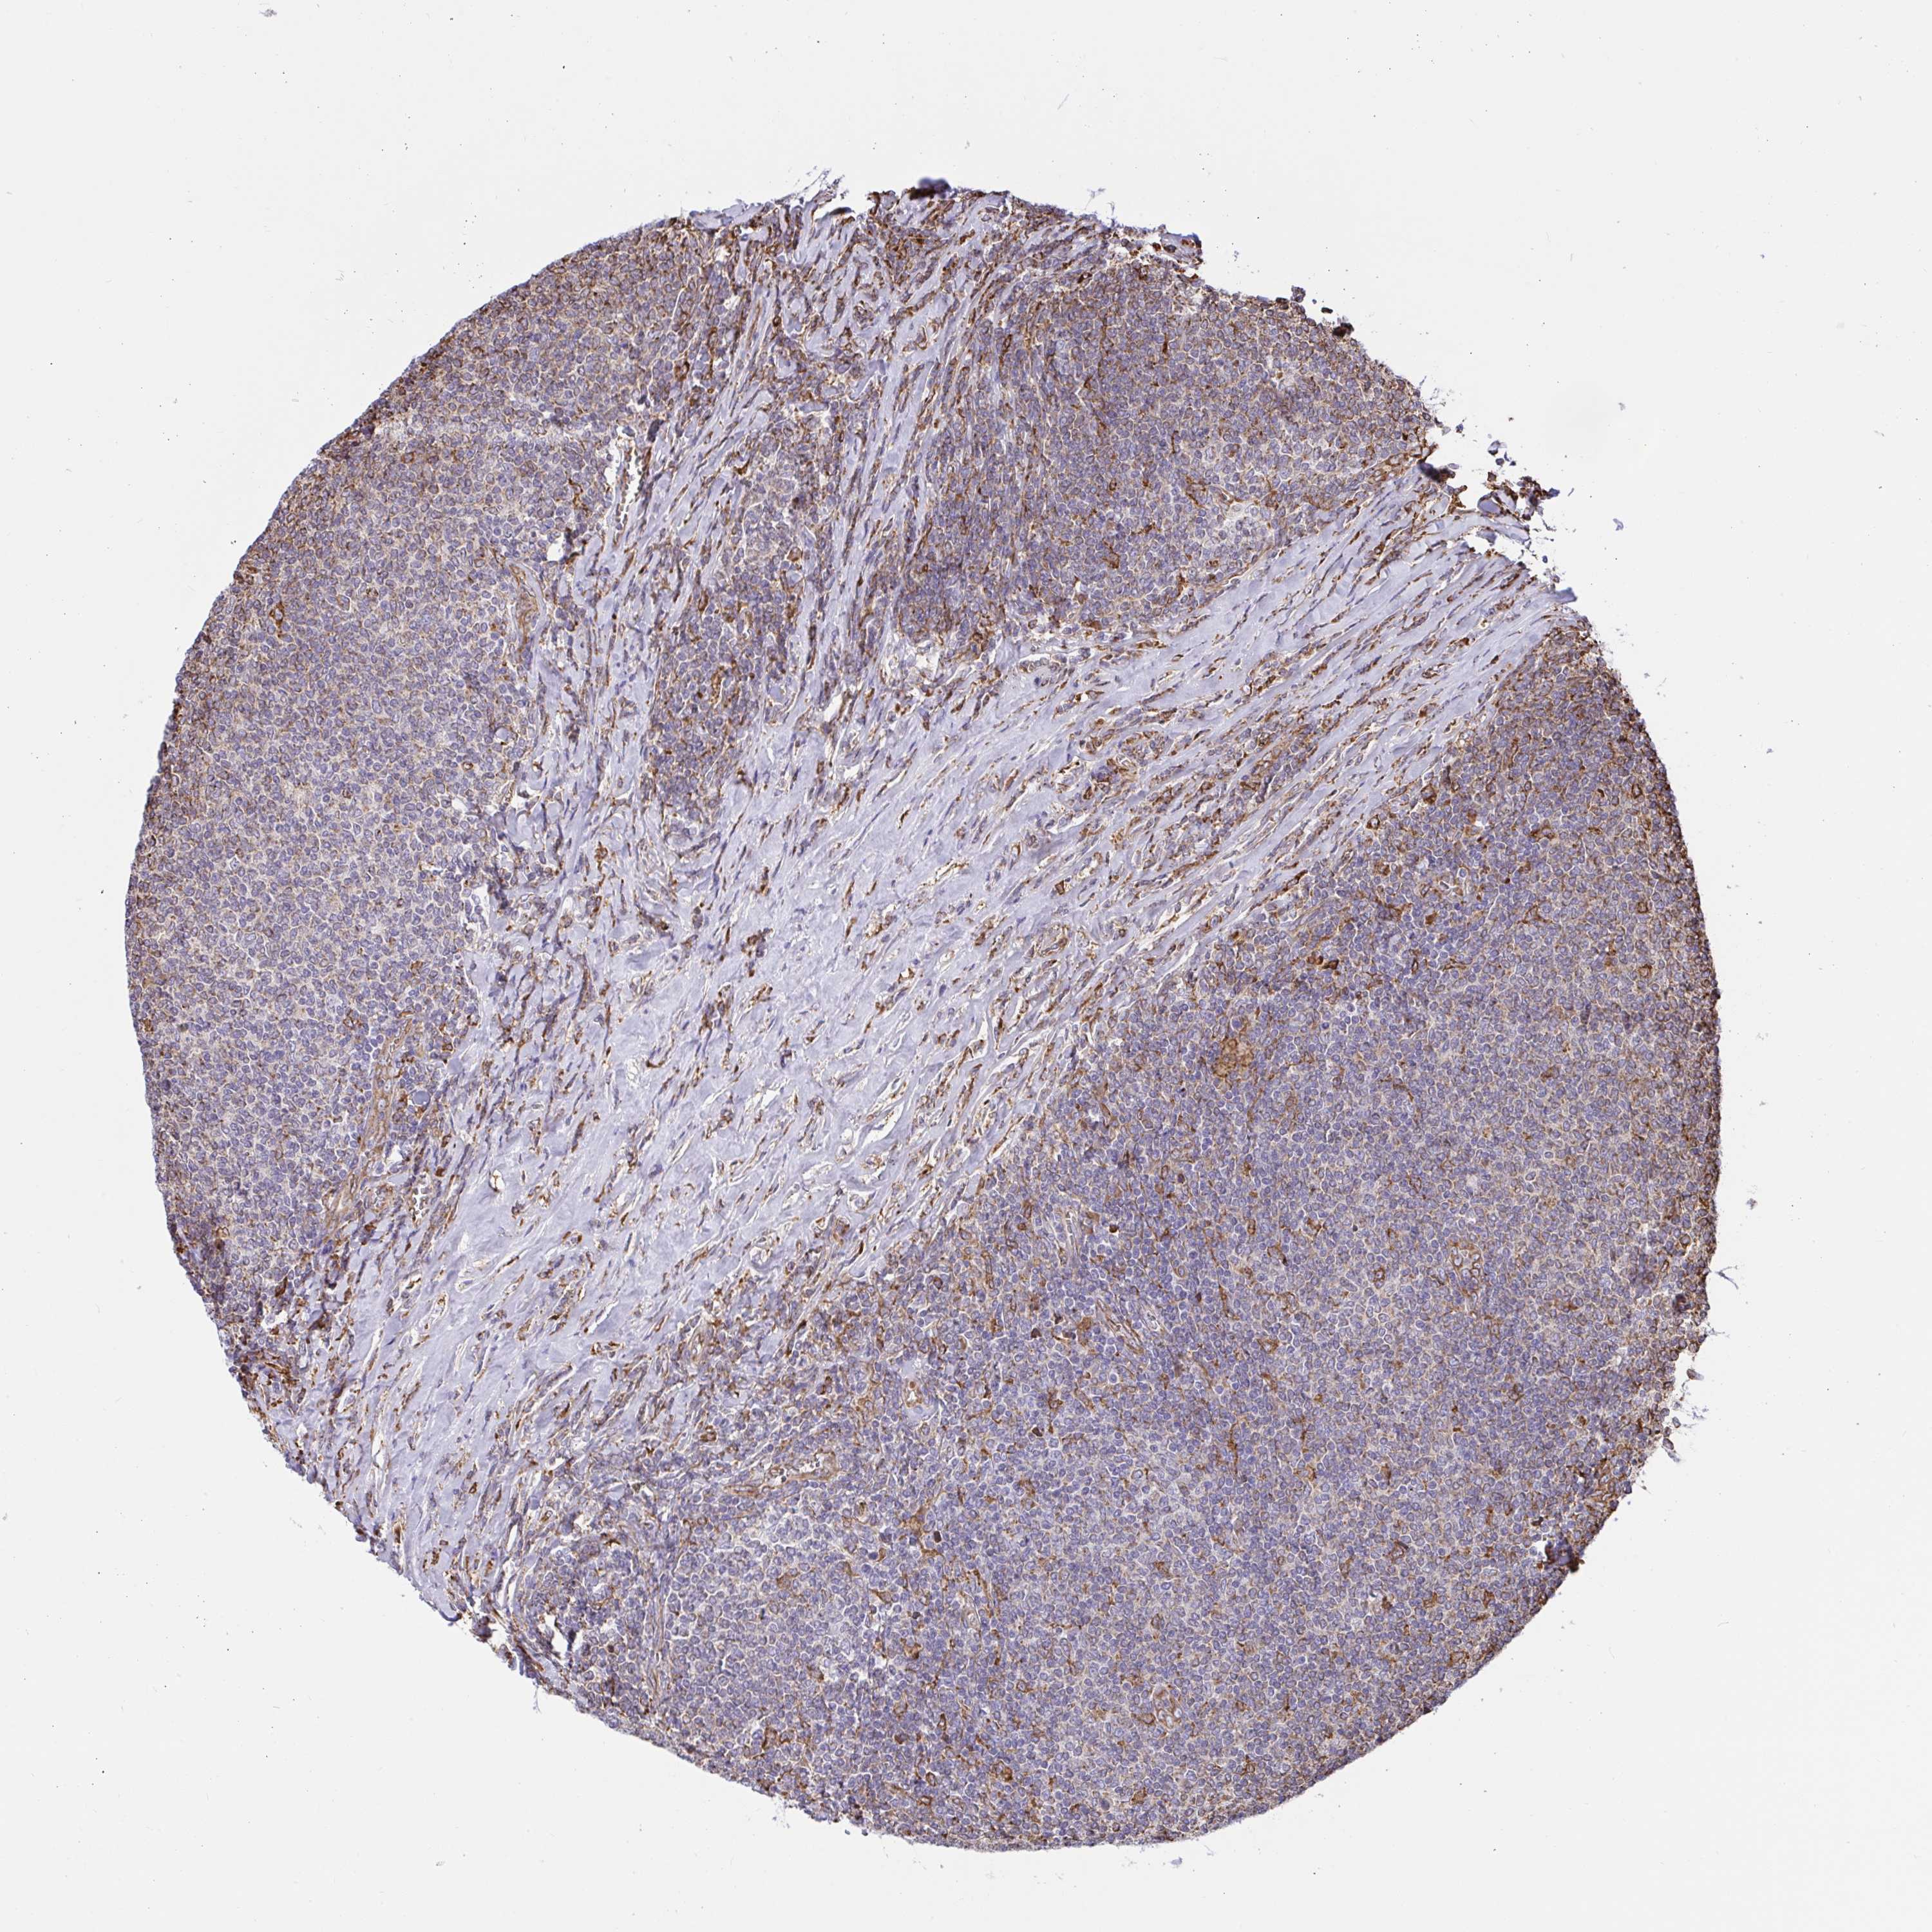

LYMPHOMA - Protein expressioni

A mouse-over function shows sample information and annotation data. Click on an image to view it in a full screen mode. Samples can be filtered based on level of antibody staining by selecting one or several of the following categories: high, medium, low and not detected. The assay and annotation is described here.

Antibody stainingi

Antibody staining in the annotated cell types in the current human tissue is reported as not detected, low, medium, or high, based on conventional immunohistochemistry profiling in selected tissues. This score is based on the combination of the staining intensity and fraction of stained cells.

Each image is clickable and will lead to virtual microscopy that enables deeper exploration of all samples and also displays staining intensity scores, fraction scores and subcellular localization as well as patient and tissue information for each sample.

Antibody HPA048761

Antibody HPA058627

Antibody CAB020709

Malignant lymphoma, non-Hodgkin's type, Low grade

Malignant lymphoma, non-Hodgkin's type, High grade

Hodgkin's disease, NOS